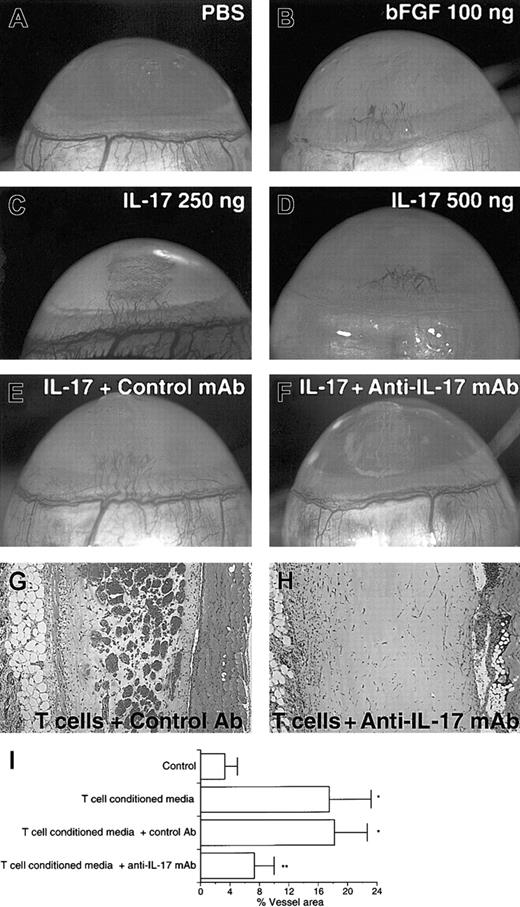

IL-17 induces neovascularization in rat cornea

To confirm that IL-17 is angiogenic in vivo, we first examined the formation of new capillary blood vessels in rat cornea assay. Implants containing 100 ng human bFGF as positive control induced angiogenic response (8 positives of 8 corneas tested) (Figure3B). Although control implants containing PBS gave no angiogenic response (Figure 3A) (no positives of 8 corneas tested), implants containing 250 or 500 ng mouse IL-17 induced significant angiogenic response (8 positives of 8 corneas tested for each dose) (Figure 3C-D). No signs of accompanying inflammatory reaction were observed as shown by the persistence of cornea transparency for the duration of the experiment. The addition of neutralizing antimouse IL-17 mAb to the implants completely abolished the IL-17–induced vascularization but not control antibody (Figure 3E-F).

IL-17 elicits neovascularization in rat cornea assay, and the addition of anti–IL-17 mAb into Matrigel suppresses the neovessel formation induced by CD4 T cells in mouse Matrigel assay.

(A) No angiogenic response to PBS was observed. (B-D) Vigorous angiogenic response to mouse IL-17 or human bFGF was observed. (E) IL-17–induced vessel formation (250 ng) was not abolished by control mAb. (F) IL-17–induced vessel formation (250 ng) was completely abolished by neutralizing anti–IL-17 mAb. (G) Matrigel plug containing CD4 T-cell–conditioned media plus 20 μg/mL control Ab. (H) Matrigel plug containing CD4 T-cell–conditioned media plus 20 μg/mL anti–IL-17 mAb. (I) Conditioned media from CD4 T cells were shown to induce neovascularization (T cells versus control;P < .05). The addition of neutralizing anti–IL-17 mAb to Matrigel resulted in marked reduction in neovessel formation elicited by CD4 T-cell–conditioned media (T cells or T cells + control Ab versus T cells + anti–IL-17 mAb; *P < .05). Results are expressed as percentage ± SD of the vessel area to the total Matrigel area assessed from 3 stained sections per Matrigel plug. Each individual experimental group included 5 mice. The result is a representative of 2 independent experiments.

Moreover, we attempted to elucidate the angiogenic activity of IL-17 secreted by CD4 T cells. Concentrated conditioned media from CD4 T cells stimulated by PMA and ionomycin were shown to induce significant neovascularization (Figure 3G). The addition of neutralizing antihuman IL-17 mAb to Matrigel resulted in marked reduction in neovessel formation (Figure 3H). These results demonstrate that most of the angiogenic activity present in the conditioned media of CD4 T cells activated in vitro was neutralizable with anti-IL-17 mAb.